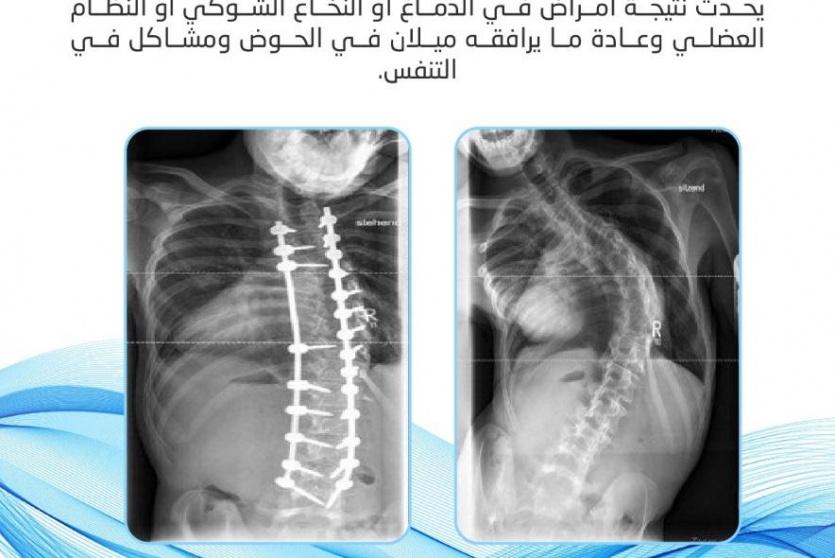

يعاني الكثير من الأشخاص من كافة الفئات بعضهم أطفال؛ من تشوهات في العمود الفقري والتي تكون عبارة عن انحناء غير طبيعي في العمود الفقري، وأكثر هذه التشوهات شيوعاً التقوس المفرط بالظهر، وتكون على درجات كالانحناء لأحد الجانبين بشكل ملفت للنظر، وهذا يؤثر سلبا على كافة جوانب حياته الشخصية والعملية.

ولفت الدكتور أبو دية إلى أن تشوهات العمود الفقري ليست وليدة عام أو عامين، بل غالبا تكون منذ الطفولة، والسبب في عدم اكتشافها مبكرا يعود إلى سببين، الأول عدم انتباه الأهل لتلك التشوهات عند الطفل، والثاني عدم متابعتها بشكل صحيح، مؤكدا أن اكتشاف المشكلة مبكرا وتم العلاج بشكل سليم، فإن الأمر لا تطور ويحتاج إلى جراحة.